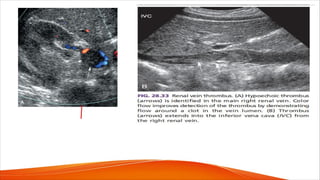

Renal vein thrombosis

• Renal vein thrombosis can be difficult to detect because of the nonspecific clinical

and radiographic findings. Acute renal vein thrombosis usually presents with pain

and hematuria and may occasionally lead to thromboembolic complications such as

pulmonary embolism.

• Chronic renal vein thrombosis may be asymptomatic or may present with nephrotic

syndrome, hematuria, or renal failure.

• Renal vein thrombosis can be caused by intraluminal tumor, thrombus formation, or

extrinsic compression.

• Associated or predisposing conditions include preexisting renal disease, renal cell

carcinoma, a hypercoagulable state, IVC or ovarian vein thrombus (with extension to

the renal veins), abdominal surgery, trauma, and dehydration.

• Primary renal disease is the most common predisposing factor, particularly the

nephrotic syndrome and membranous glomerulonephritis

• With acute thrombosis, the renal vein is invariably enlarged, and Doppler signals are

absent. A small trickle of flow may be present around the clot, with low-velocity,

continuous Doppler signals (lacking respiratory phasicity).

• Recently formed thrombus is hypoechoic and in some cases appears anechoic. As a

result, the thrombus may not be readily seen with gray-scale sonography but is

detectable with color flow imaging.